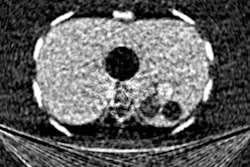

The researchers enrolled 91 patients who underwent CT scans for suspected emphysema and who were diagnosed at varying stages, from no emphysema to mild, moderate, and advanced destructive disease. Dark-field and attenuation-based radiographs were acquired simultaneously in the patients at a radiation dose of 0.035 mSv.

For each patient, three radiologist readers then evaluated conventional x-ray images alone, dark-field images alone, or both images displayed together for the presence and severity of disease. The CT scans served as ground truth.

Doctoral candidate Theresa Urban of the Technical University of Munich presented the first clinical trial evidence evaluating dark-field chest radiography during ECR 2022 Overture.The dark-field images showed varying signal strengths based on the severity of emphysema, which confirmed its sensitivity for detecting the extent of damage in alveoli microstructures.